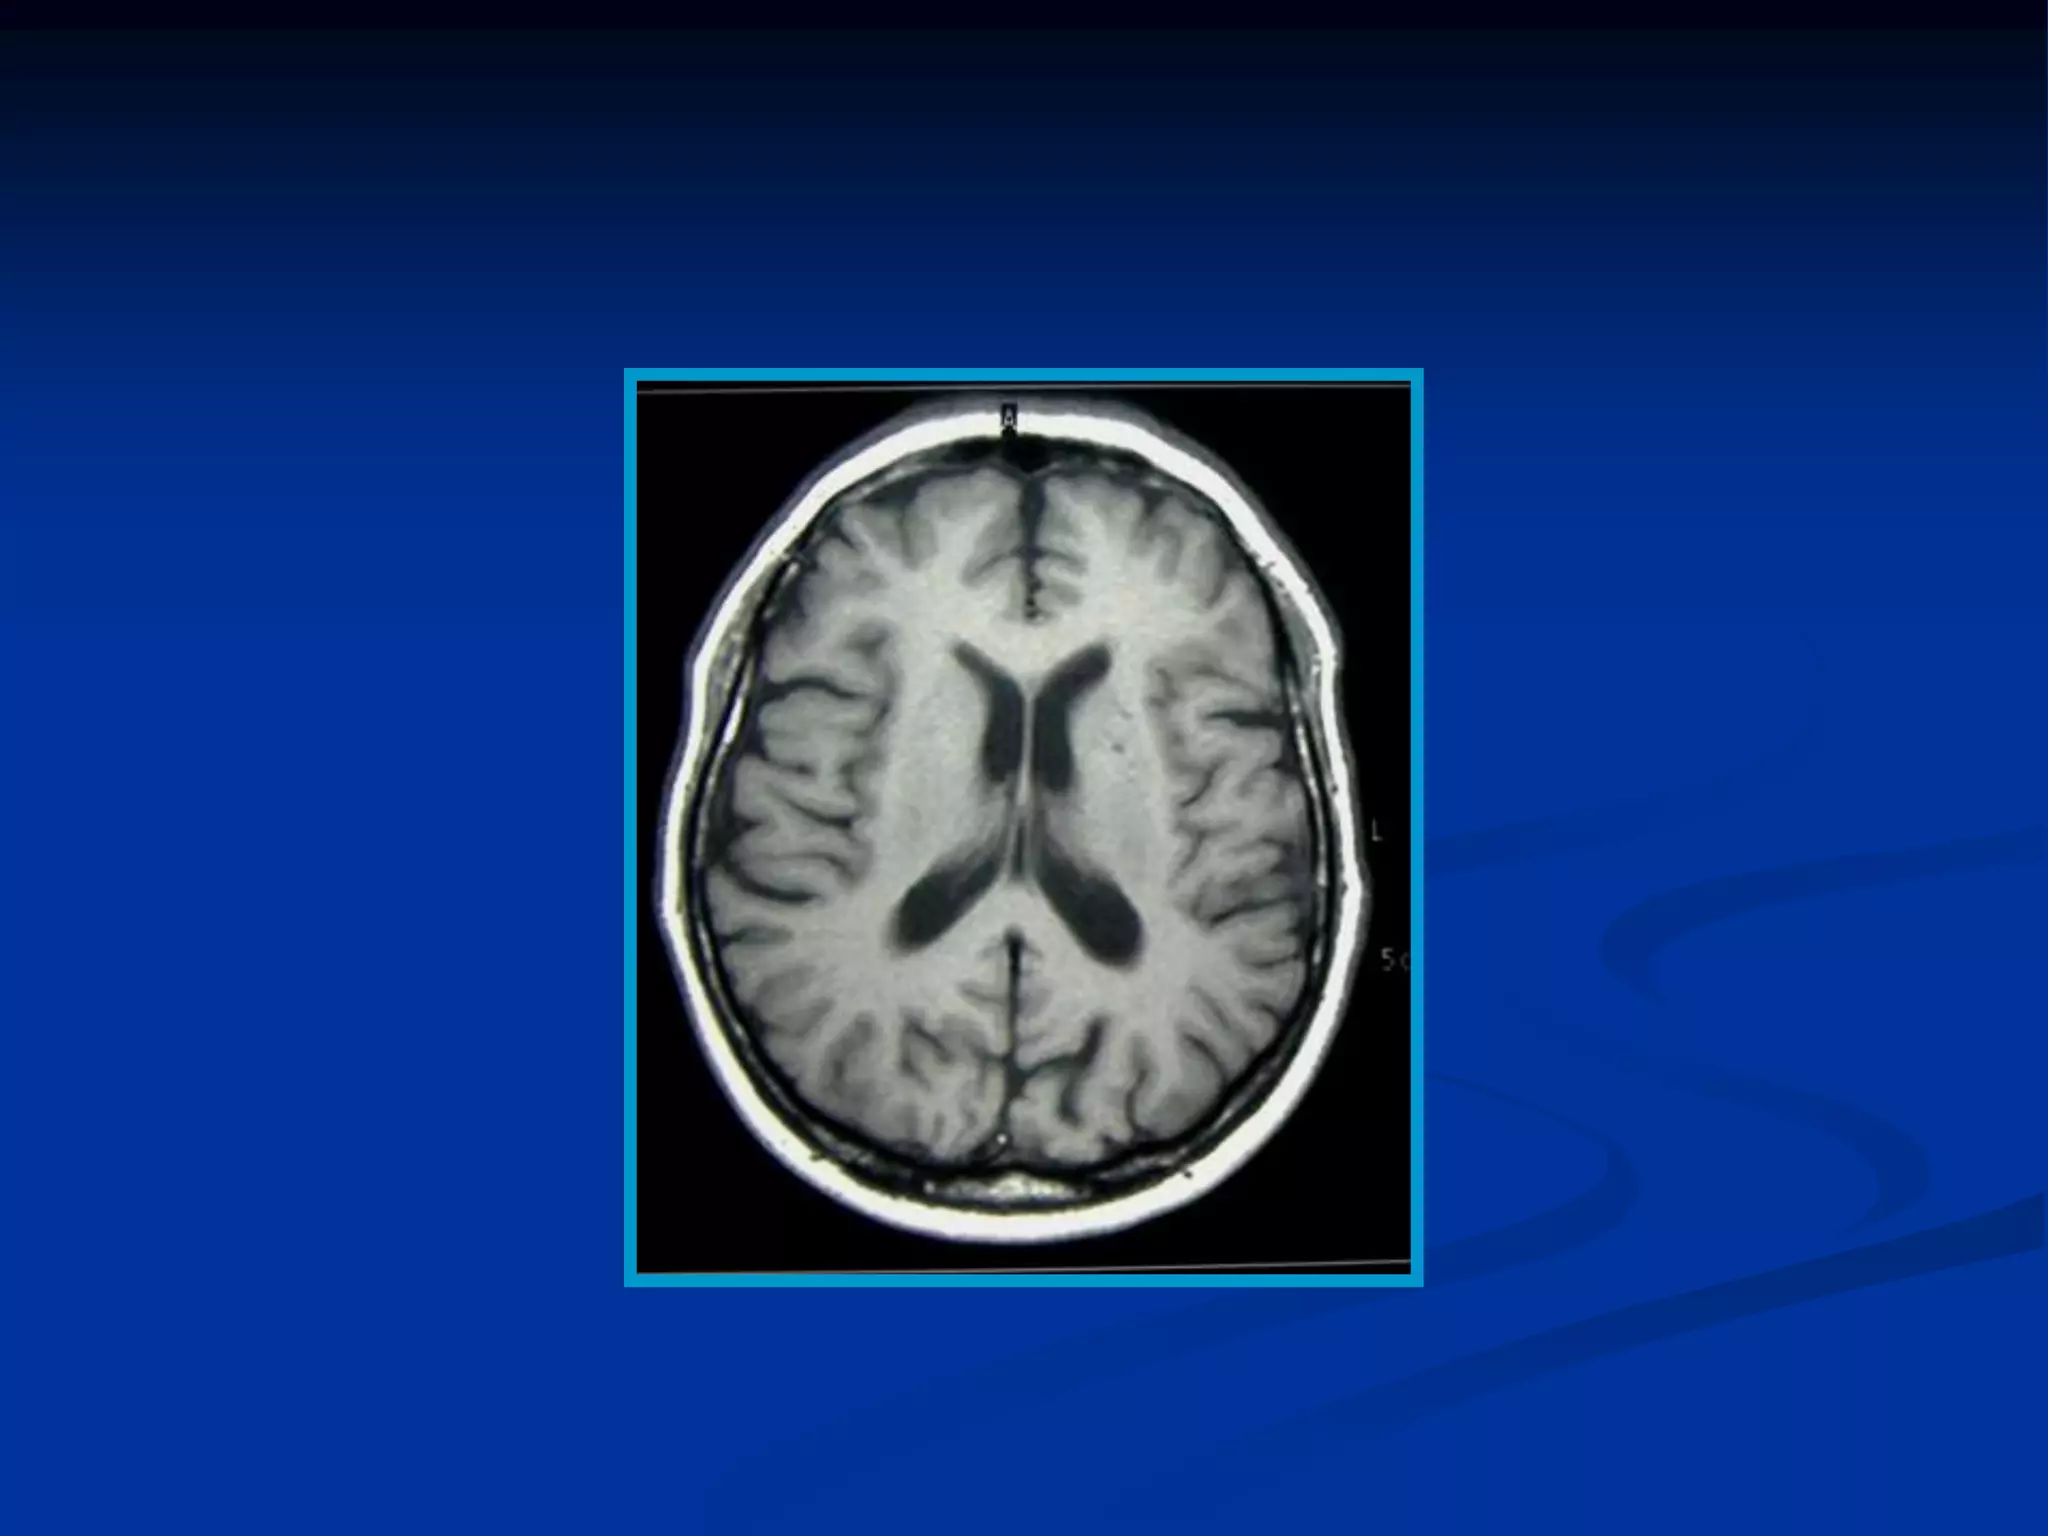

Imágenes potenciadas en T1 de los diferentes

tejidos según su grado de relajacion T1 en un

momento determinado

   Los tejidos con un T1 mas corto, como la grasa

muestran mayor intensidad de

señal, (hiperintensa o blanco en la imagen).

   El hígado tiene un T1 mas corto que el bazo y

su señal es mas intensa que la del bazo.

tejidos según su grado de relajación T1 en un

Imágenes potenciadas enT1 de los diferentes tejidos según su grado de relajacion T1 en un momento determinado  Los tejidos con un T1 mas corto, como la grasa muestran mayor intensidad de señal, (hiperintensa o blanco en la imagen).  El hígado tiene un T1 mas corto que el bazo y su señal es mas intensa que la del bazo.

Imágenes potenciadas enT1 de los diferentes tejidos según su grado de relajación T1 en un momento determinado • En el cerebro el LCR, tiene un T1 largo y la señal es hipointensa. • La sustancia gris tiene menor intensidad de señal (agua) que la sustancia blanca (grasa)